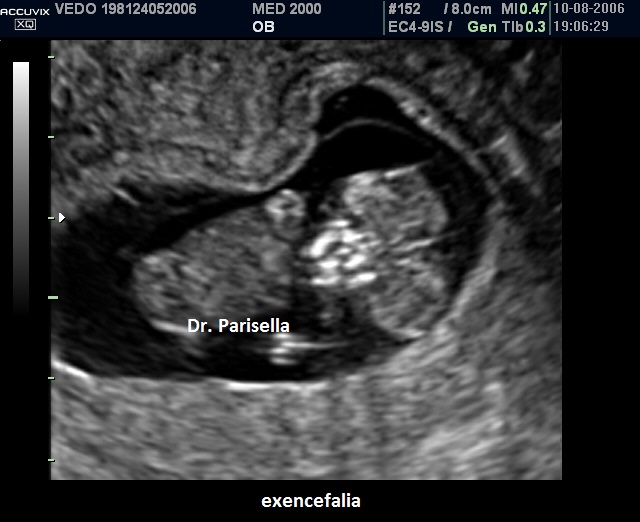

Nel I trimestre il processo distruttivo dell'encefalo non è ancora evidente per cui in questo periodo si osserva solo la mancata ossificazione delle ossa della volta cranica mentre gli emisferi cerebrali appaiono normali: si parla di acrania-exencefalia.

Alla fine del I trimestre il contatto dell'encefalo col liquido amniotico determina la distruzione del tessuto cerebrale con trasformazione dell'exencefalia in anencefalia.

Dopo la 12a settimana per il diretto contatto col liquido amniotico ed i traumi determinati dal contatto con la parete uterina l'encefalo si trasforma in una massa di tessuto molle aderente alla base del cranio determinandosi il quadro dell'anencefalia caratterizzato dall'assenza della volta cranica e da tessuto cerebrale scarsamente rappresentato.